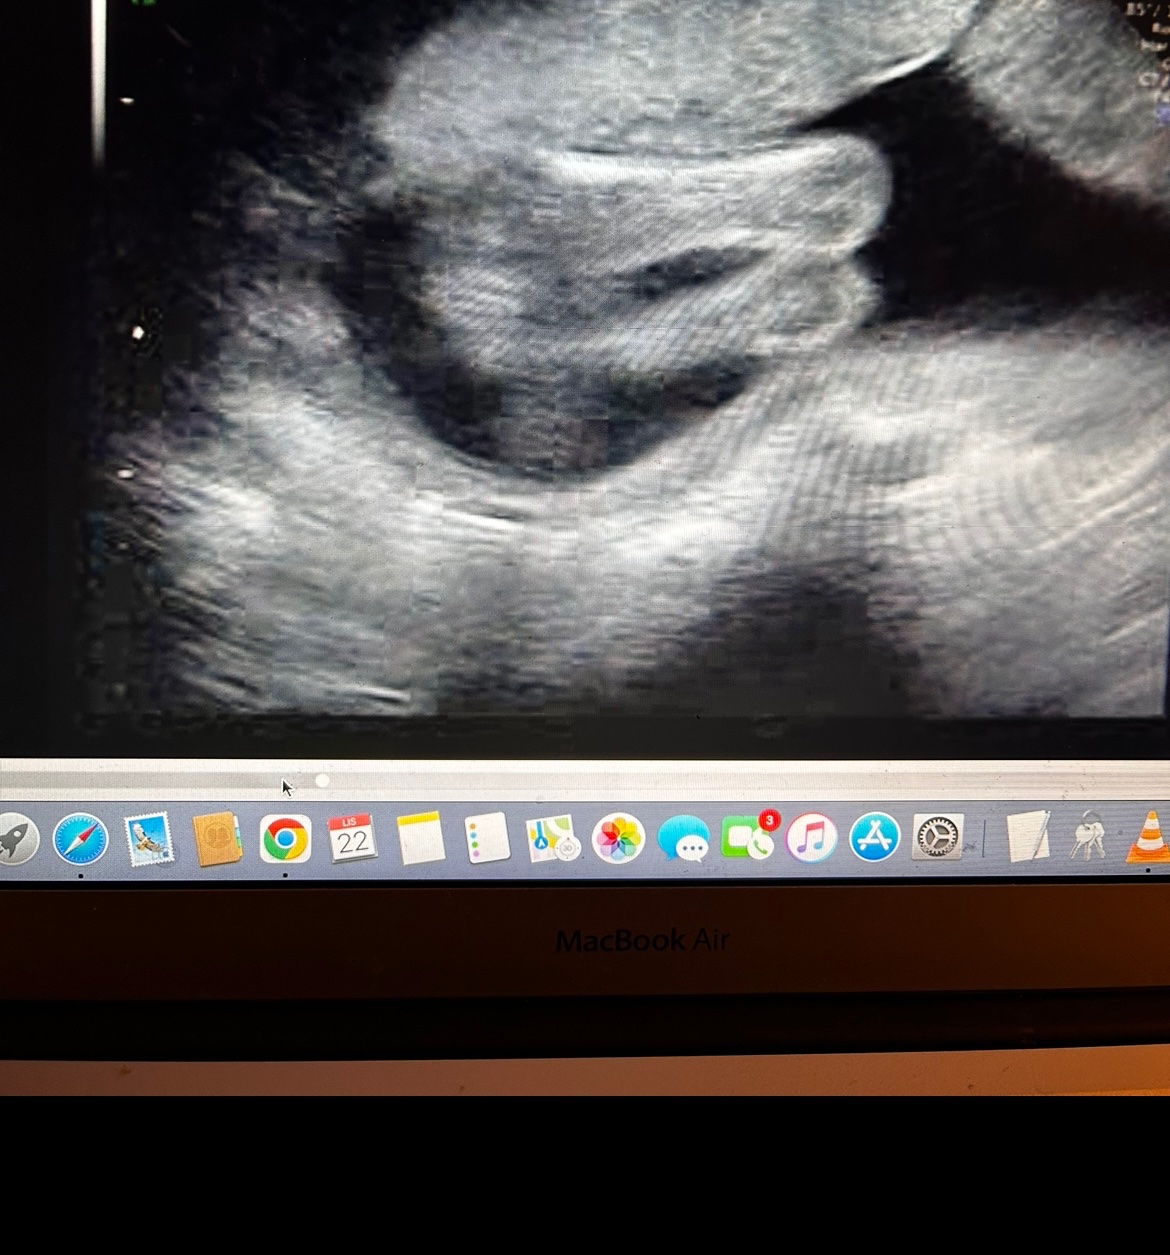

Holčička nebo chlapeček? Co vidíte na obrázku?

Dobrý večer všem, co vidíte? Díky za názory 🙂

Holka